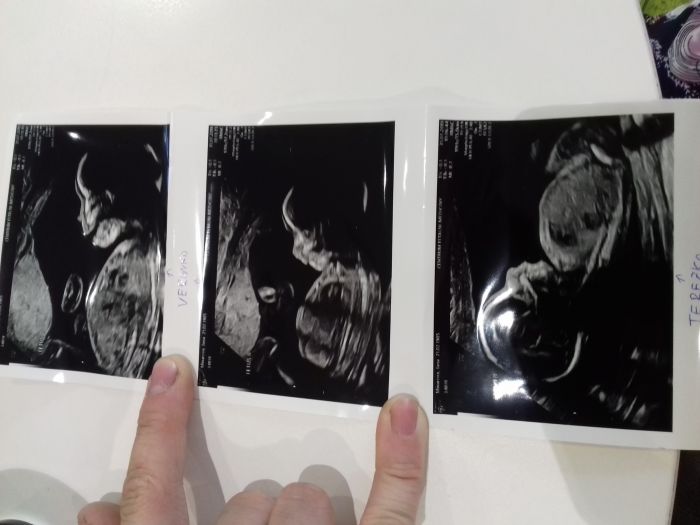

Ahojky holky, tak mam po screeningu a vse je v pořádku. Holčičky mají obě 320g což je super. Krasne se tam vrtely. I srdicka máme v pořádku. Paní doktorky byly nadmíru spokojene a ja sem taky. Už tak 3 dny je cítím víc tak sem stastna.

janamin gratuluju ke screeningu . krásné holčičky. jen mám blbou otázku . všimla jsem si že jsou fotky pojmenované. jak poznáš příště nebo až se narodí že např. ta terezka je terezka?

Oni si jména holčiček už zapsaly i do zprávy. Miminko A je Verunka a miminko B je Terezka tak si to snad budou pamatovat a budou to mit napsaný v počítači. Budou to vědět taky podle uložení miminek.

JanaMin, hlavne at je pri porodu zpravne pojmenuji, co kdyz se holky v brisku prestehuji?